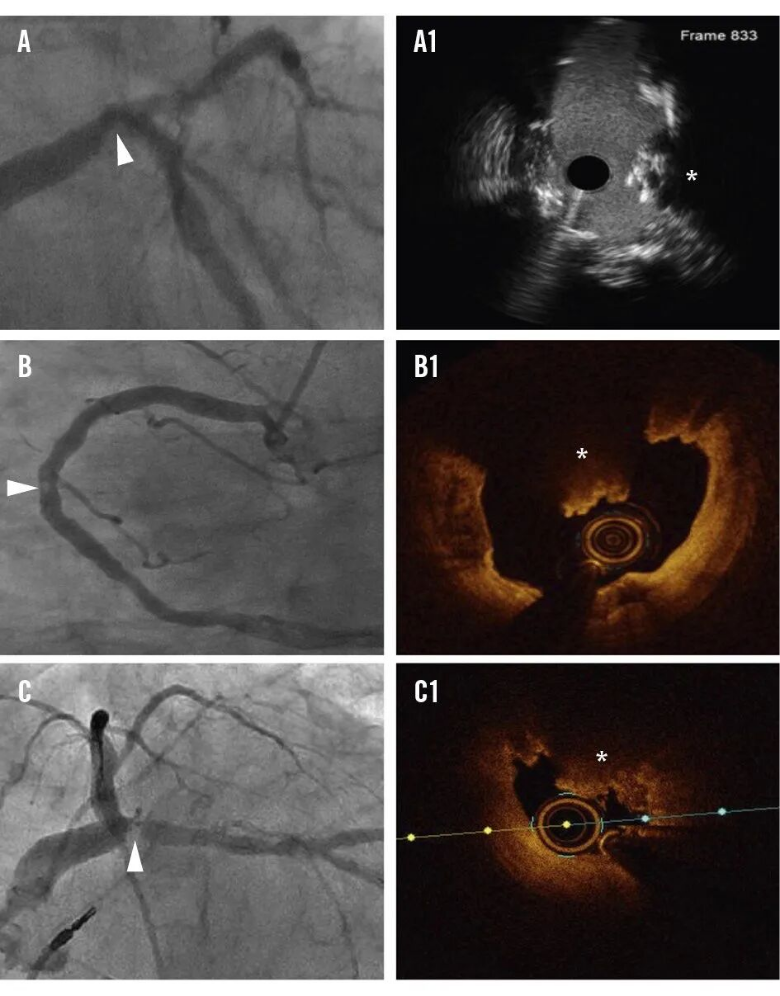

图6.钙化结节的冠状动脉造影特征。冠状动脉造影特征,CNs呈透亮区(白色箭头)。IVUS (A1)和OCT (B1,C1)证实钙化结节。CN:钙化结节(calcified nodule)。

血管内超声(IVUS)

普通IVUS可见强回声伴声影,高分辨率IVUS(HD-IVUS)可判断纤维帽是否连续,区分爆发型(破裂)与非爆发型(完整)。

图7.IVUS可显示和区别不同类型的钙化病变。A和B为爆发型钙化结节,在IVUS上表现为凸入管腔的不规则簇状钙化团块,表面不规则,常伴强后方声影和可能血栓低回声信号。C-F为各种形态的非爆发型钙化结节,在IVUS上表现为凸入管腔的团块状或盘状钙化,表面相对光滑、纤维帽较完整,后方伴声影但无明显簇状不规则结构。(IVUS设备:Boston Scientific OptiCross HD 60MHz)

光学相干断层成像

光学相干断层扫描(OCT)是诊断CN的金标准,分辨率高。爆发型CN表现为表面不规则、纤维帽破裂、血栓覆盖。非爆发型CN则表面光滑、纤维帽完整。